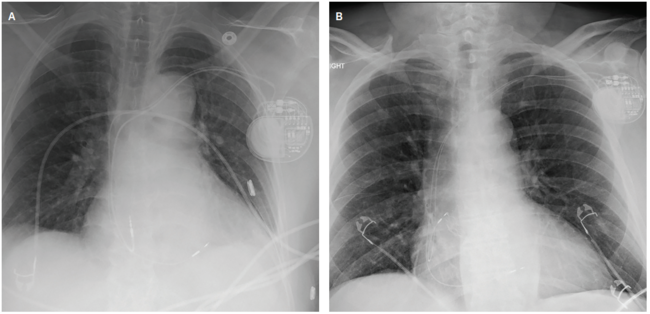

Verification of the BB location during implantation has been achieved through various methods. Early studies defined BB pacing fluoroscopically.11 In 2008, Saremi et al4 reported that BB and its vascular supply could be identified on cardiac computed tomography, but were less easily seen in patients with severe coronary artery disease or abnormal ECG findings. A 2022 case series used fluoroscopic and electrical mapping to identify the endocardial electrogram signature of the BB region and associated BB potentials.21 P-wave axis and morphology, along with the local electrogram signal at or near BB, were also used for localization. In 2025, investigators

(Images provided by Zachary Hollis MD, personal communication, October 2025. Images courtesy of Zachary Hollis MD, used with permission.)

evaluated electrogram-guided BB pacing using sheath-assisted, stylet-driven atrial lead implantation.22 They incorporated 12-lead P-wave morphology and electrogram analysis, recorded BB potentials in most patients, and performed threshold testing that demonstrated BB capture in >80%. (Figure 2)